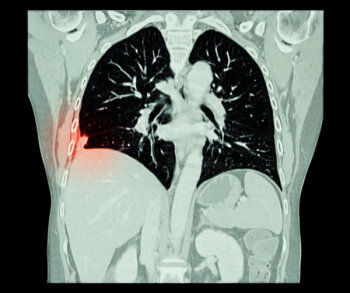

In a study of over 1,000 patients who had surgery for invasive lung adenocarcinoma, researchers found that solid adenocarcinoma on pre-op CT imaging was associated with more than double the risks of recurrence and brain metastasis in patients with clinical stage I disease in comparison to ground-glass opacity (GGO) adenocarcinoma.